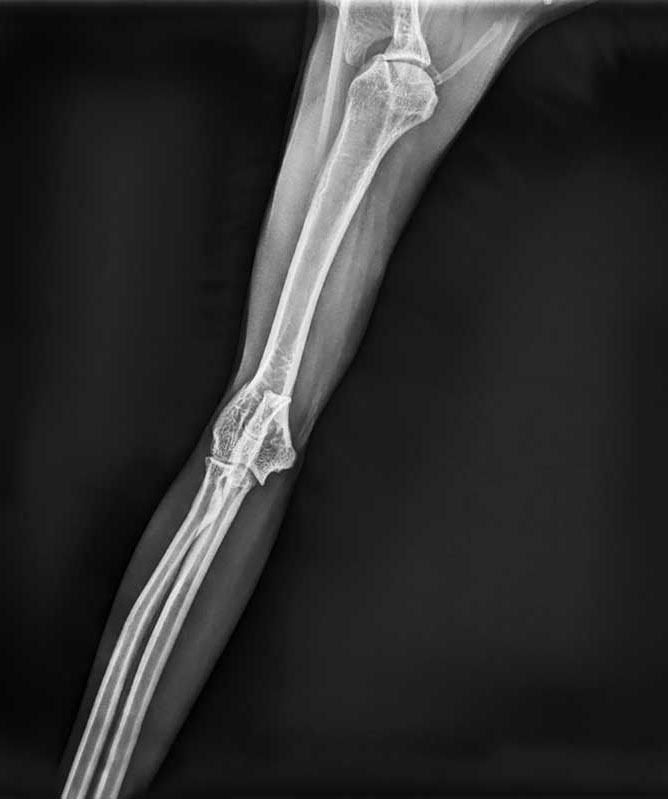

Feline elbow radiograph showing mild degenerative joint disease (DJD) apparent on the cranial caudal view.

Photos courtesy MinXray